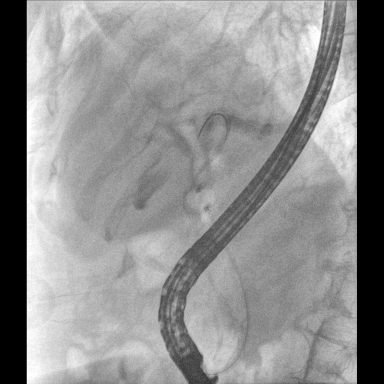

具备血管造影及数字减影(DSA)、路径图(Road-map)、透视、摄影等功能。 广泛适用于介入科、血管外科、肿瘤科、消化内科及骨科等多个临床科室,典型应用包括:TACE(肝肿瘤栓塞与化疗灌注术)、心脏起搏器置入术、四肢动脉造影术、下肢静脉滤器置入术、ERCP(经内镜逆行胰胆管造影术)等。

核心DSA软件可实时生成高清血管影像,结合路径图功能,在手术中为医生提供血管导航。

设备搭载自主研发的大功率高压发生器、高热容球管与大尺寸平板探测器,配合先进图像处理算法及高效冷却循环系统,能够在长时间手术过程中持续输出高清图像并保持帧率稳定。

预留高压注射器联动接口,C形臂开始透视时,高压注射器自动注入造影剂,提高术中造影减影效率,减少医师手推造影剂所受到的辐射暴露剂量。